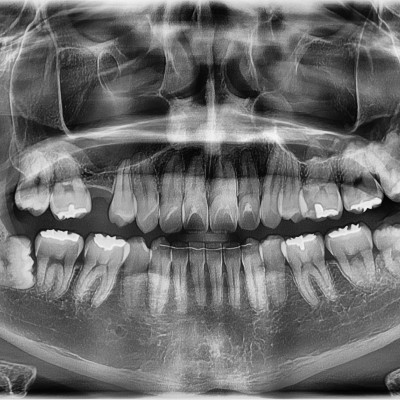

#18,28,38,48 사랑니 발치 #18,28,38,48 사랑니 발치 구강 외과 전문의가 당일 발치했습니다. ------------------..